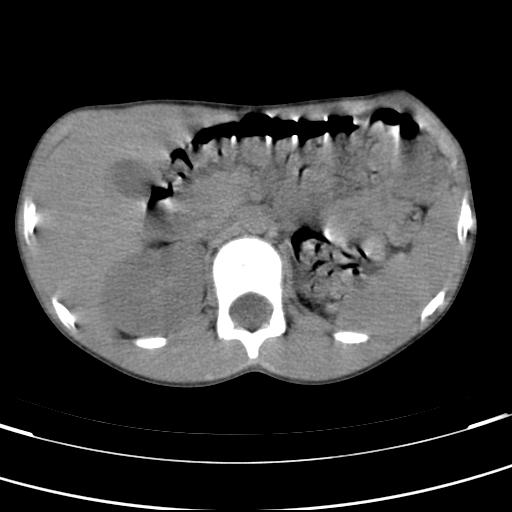

标题: PED3157:左肾缺如,请教脾脏的改变?、、

男孩,9岁。胃部不适。

脾脏变异,左肾未见,游走、异位、发育不全都要可能,增强或ivp造影。

脾脏位于左侧,但数个脾脏呈分离状态,左肾缺如,右肾代偿肥大。考虑多脾综合征。